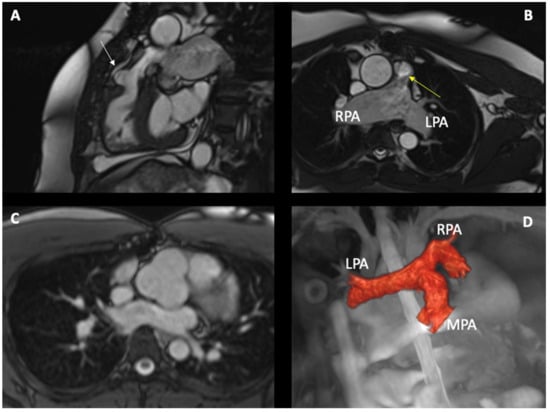

3. Cardiovascular Magnetic Resonance in Tetralogy of Fallot

3.1. Introduction

3.2. CMR Sequences in Tetralogy of Fallot

3.3. CMR Findings in Tetralogy of Fallot

- Ojha, V.; Pandey, N.N.; Sharma, A.; Ganga, K.P. Spectrum of changes on cardiac magnetic resonance in repaired tetralogy of Fallot: Imaging according to surgical considerations. Clin. Imaging 2021, 69, 102–114. [Google Scholar] [CrossRef]